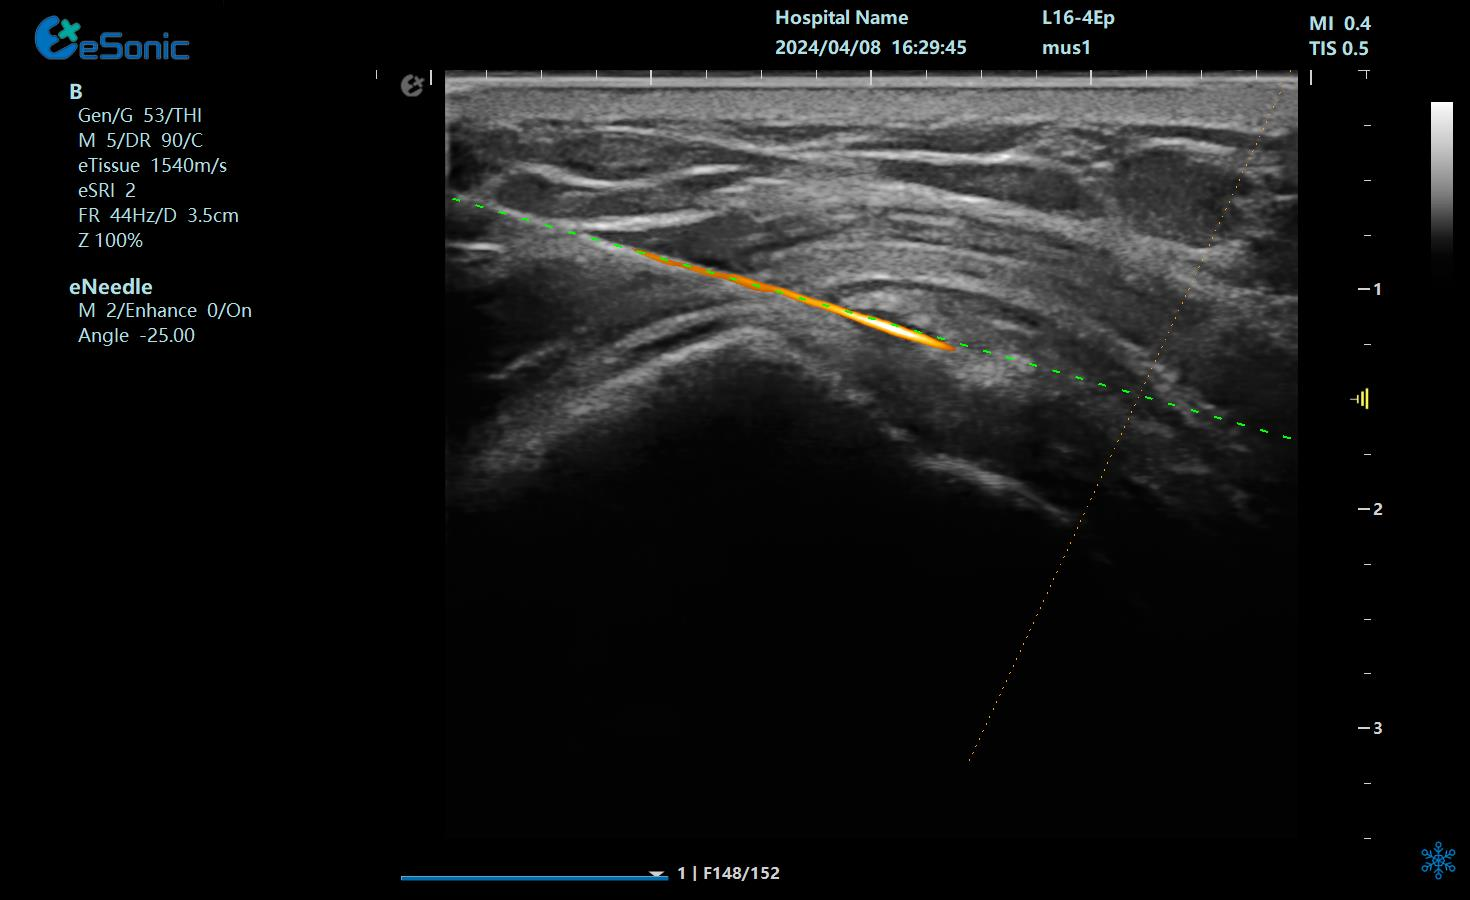

在超声图像中,穿刺针和钙化灶的显示都为强回声,常规的超声引导穿刺即使增强了穿刺针的显示仍不能有效地区分针尖和钙化灶,可能导致对穿刺部位的判断失误,往往比较依赖于医生的经验穿刺到钙化灶。

治疗中使用穿刺针智能Map和无磁导航技术